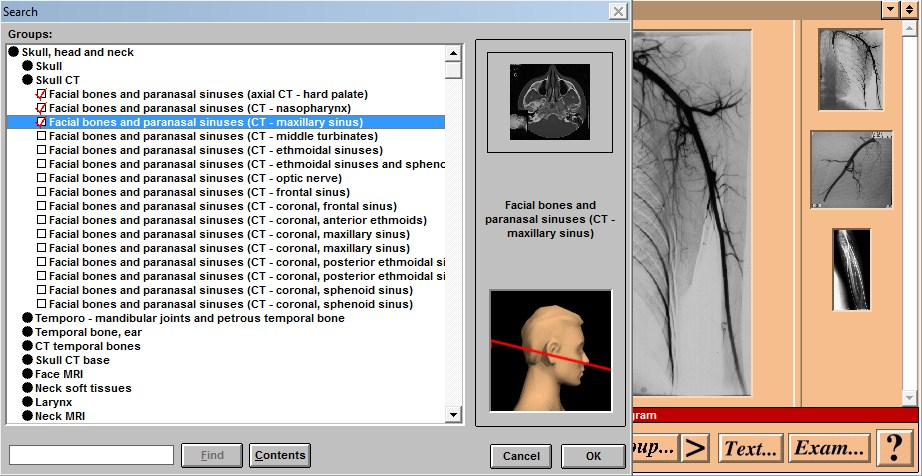

Windows Совместимость с Vista: неизвестно Системные требования: IBM or compatible PC, 486SX, 8MB RAM, 640 × 480 display, 256 colors, double speed CD-ROM drive, Microsoft Windows 3.1 or later, optimum: Pentium processor, 800 × 600 display, more than 256 colors, ISBN 0-7234-2187-0, St Louis, Mo, Mosby, 1995 Язык интерфейса: только английский Таблэтка: Не требуется Описание: This CD-ROM provides a detailed atlas of radiologic anatomy in all forms, including plain films, magnetic resonance (MR) imaging, computed tomography (CT), venography, and angiography. It is formatted to present a concise atlas, cephalad (skull) to caudad (feet). The disc is easy to work with, and I did not have any trouble setting it up. The graphics and table of contents are laid out well. Navigating the various parts is relatively simple. The opening graphics are well displayed, allowing instant access to pictures or the table of contents; therein lies the simplicity of finding an anatomical part of the body to review. Each screen contains a picture of the radiograph accessed, key landmarks (with a glossary that can be turned off), related slides that can easily be accessed, and a self-exam. Диск содержит более чем 3500 радиографических изображений нормальной анатомии, включая обычные рентгенограммы, КТ, МРТ, ангиограммы, артериограммы и видео УЗИ. Исчерпывающий уровень анатомических ориентиров с возможностью самоконтроля. Издание рассчитано прежде всего на рентгенологов. Доп. информация: Поскольку издание старое, придется установить древнюю версию Quick Time - 2.0.3.51 (есть на самом диске). Набор в группу «Хранители» - Помогите сохранить редкие раздачи Программы и Дизайн » Системы для бизнеса, офиса, научной и проектной работы » Медицина - интерактивный софт